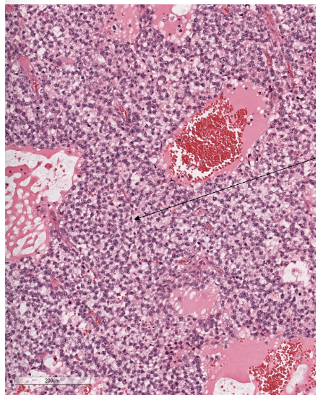

What is shown here?

Testis

Lot of abnormal cells

Infiltration of lymphocytes

Blood vessels

What is shown here and what is the label?

Little bit of invasion of normal testicular structure

What is labelled and what is shown here?